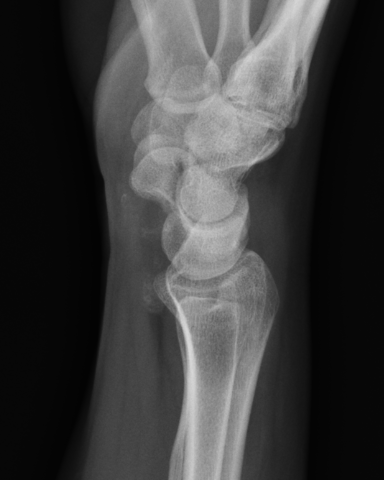

X-ray

Demonstrate calcified lesions / synovial osteochondromatosis